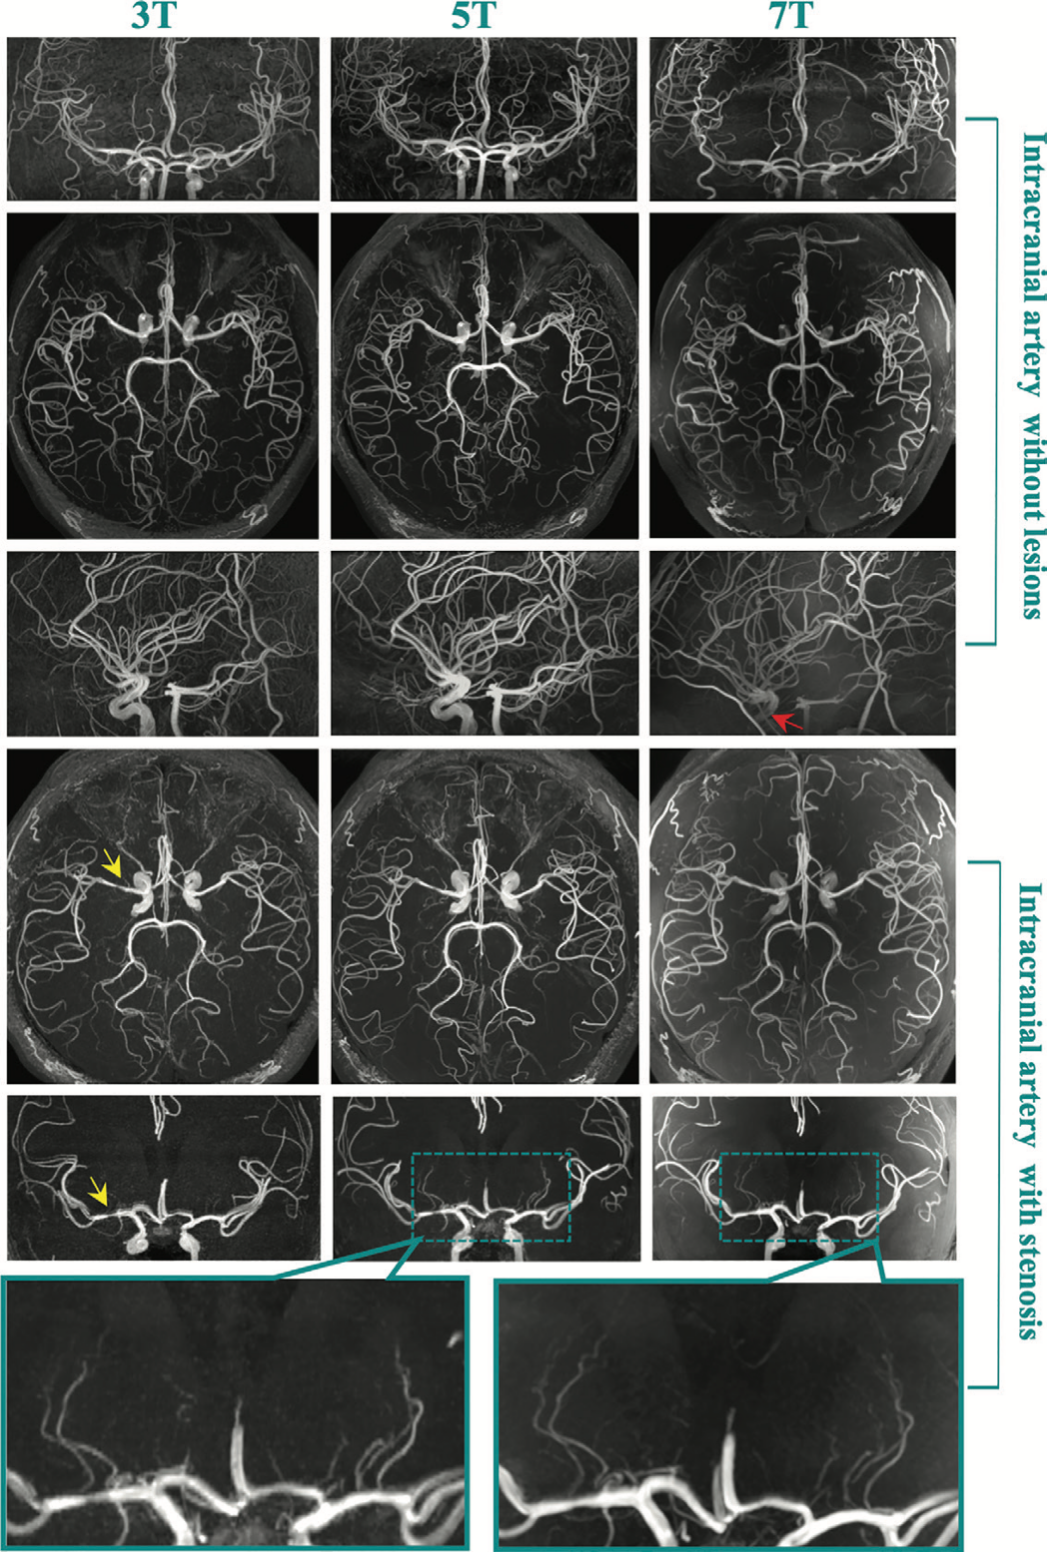

本研究采用前瞻性、完全区组设计,并获得2026年足球世界杯直播附属中山医院伦理委员会批准(伦理号2021-073R2),将每位入组受试者在48小时内分别进行3.0T、5.0T和7.0T三种不同场强但相同扫描参数条件的颅内血管TOF-MRA检查,所获图像由两名放射科医生进行评分,同时采用血管自动分割软件进行定量分析(包括脑血管的总长度、总体积等)。按照纳、排标准最终分析了12位受试者(其中健康人10位,曾患有脑血管疾病者2位,平均年龄38±9岁,男性9人)。研究结果表明,三种场强TOF-MRA的信噪比(SNR)和对比噪声比(CNR)均随场强增高而增高,但5.0T的SNR和CNR与7.0T相比并无统计学差异;在脑血管的比较中,发现5.0T TOF-MRA对脑大动脉远端分支和穿支小动脉的显示在评分上均高于3.0T,但与7.0T的评分无显著差异;进一步采用定量指标对三种场强的TOF-MRA进行分析,结果发现5.0T小动脉的总长度与7.0T无统计学差异,但均明显高于3.0T。

作为科技部“十三五”重点研发专项,我国自主研发的全球首款5.0 T高场全身MR成像系统uMR Jupiter 5.0 T在权衡高场强以及全身成像之间的矛盾关系后突破了高场射频技术壁垒,研制了大孔径多通道体发射线圈,使全身扫描成为可能。为了进一步拓展5.0 T MR的临床应用,中山医院放射科在曾蒙苏教授的指导下,通过TOF-MRA对脑内大血管远段分支和重要穿支动脉的显示进行初步评估,认为在脑动脉及其细小分支动脉的显示上5.0T TOF-MRA表现优异,前期回顾性研究也已发表于2022年8月第56卷第8期《中华放射学杂志》,为后续脑血管疾病的诊断和鉴别诊断做好技术铺垫。同时,与既往研究相比,本研究在主要分支血管的评估中加入了后循环穿支动脉(脑桥动脉)评估,为全面评估脑小动脉做好研究铺垫。